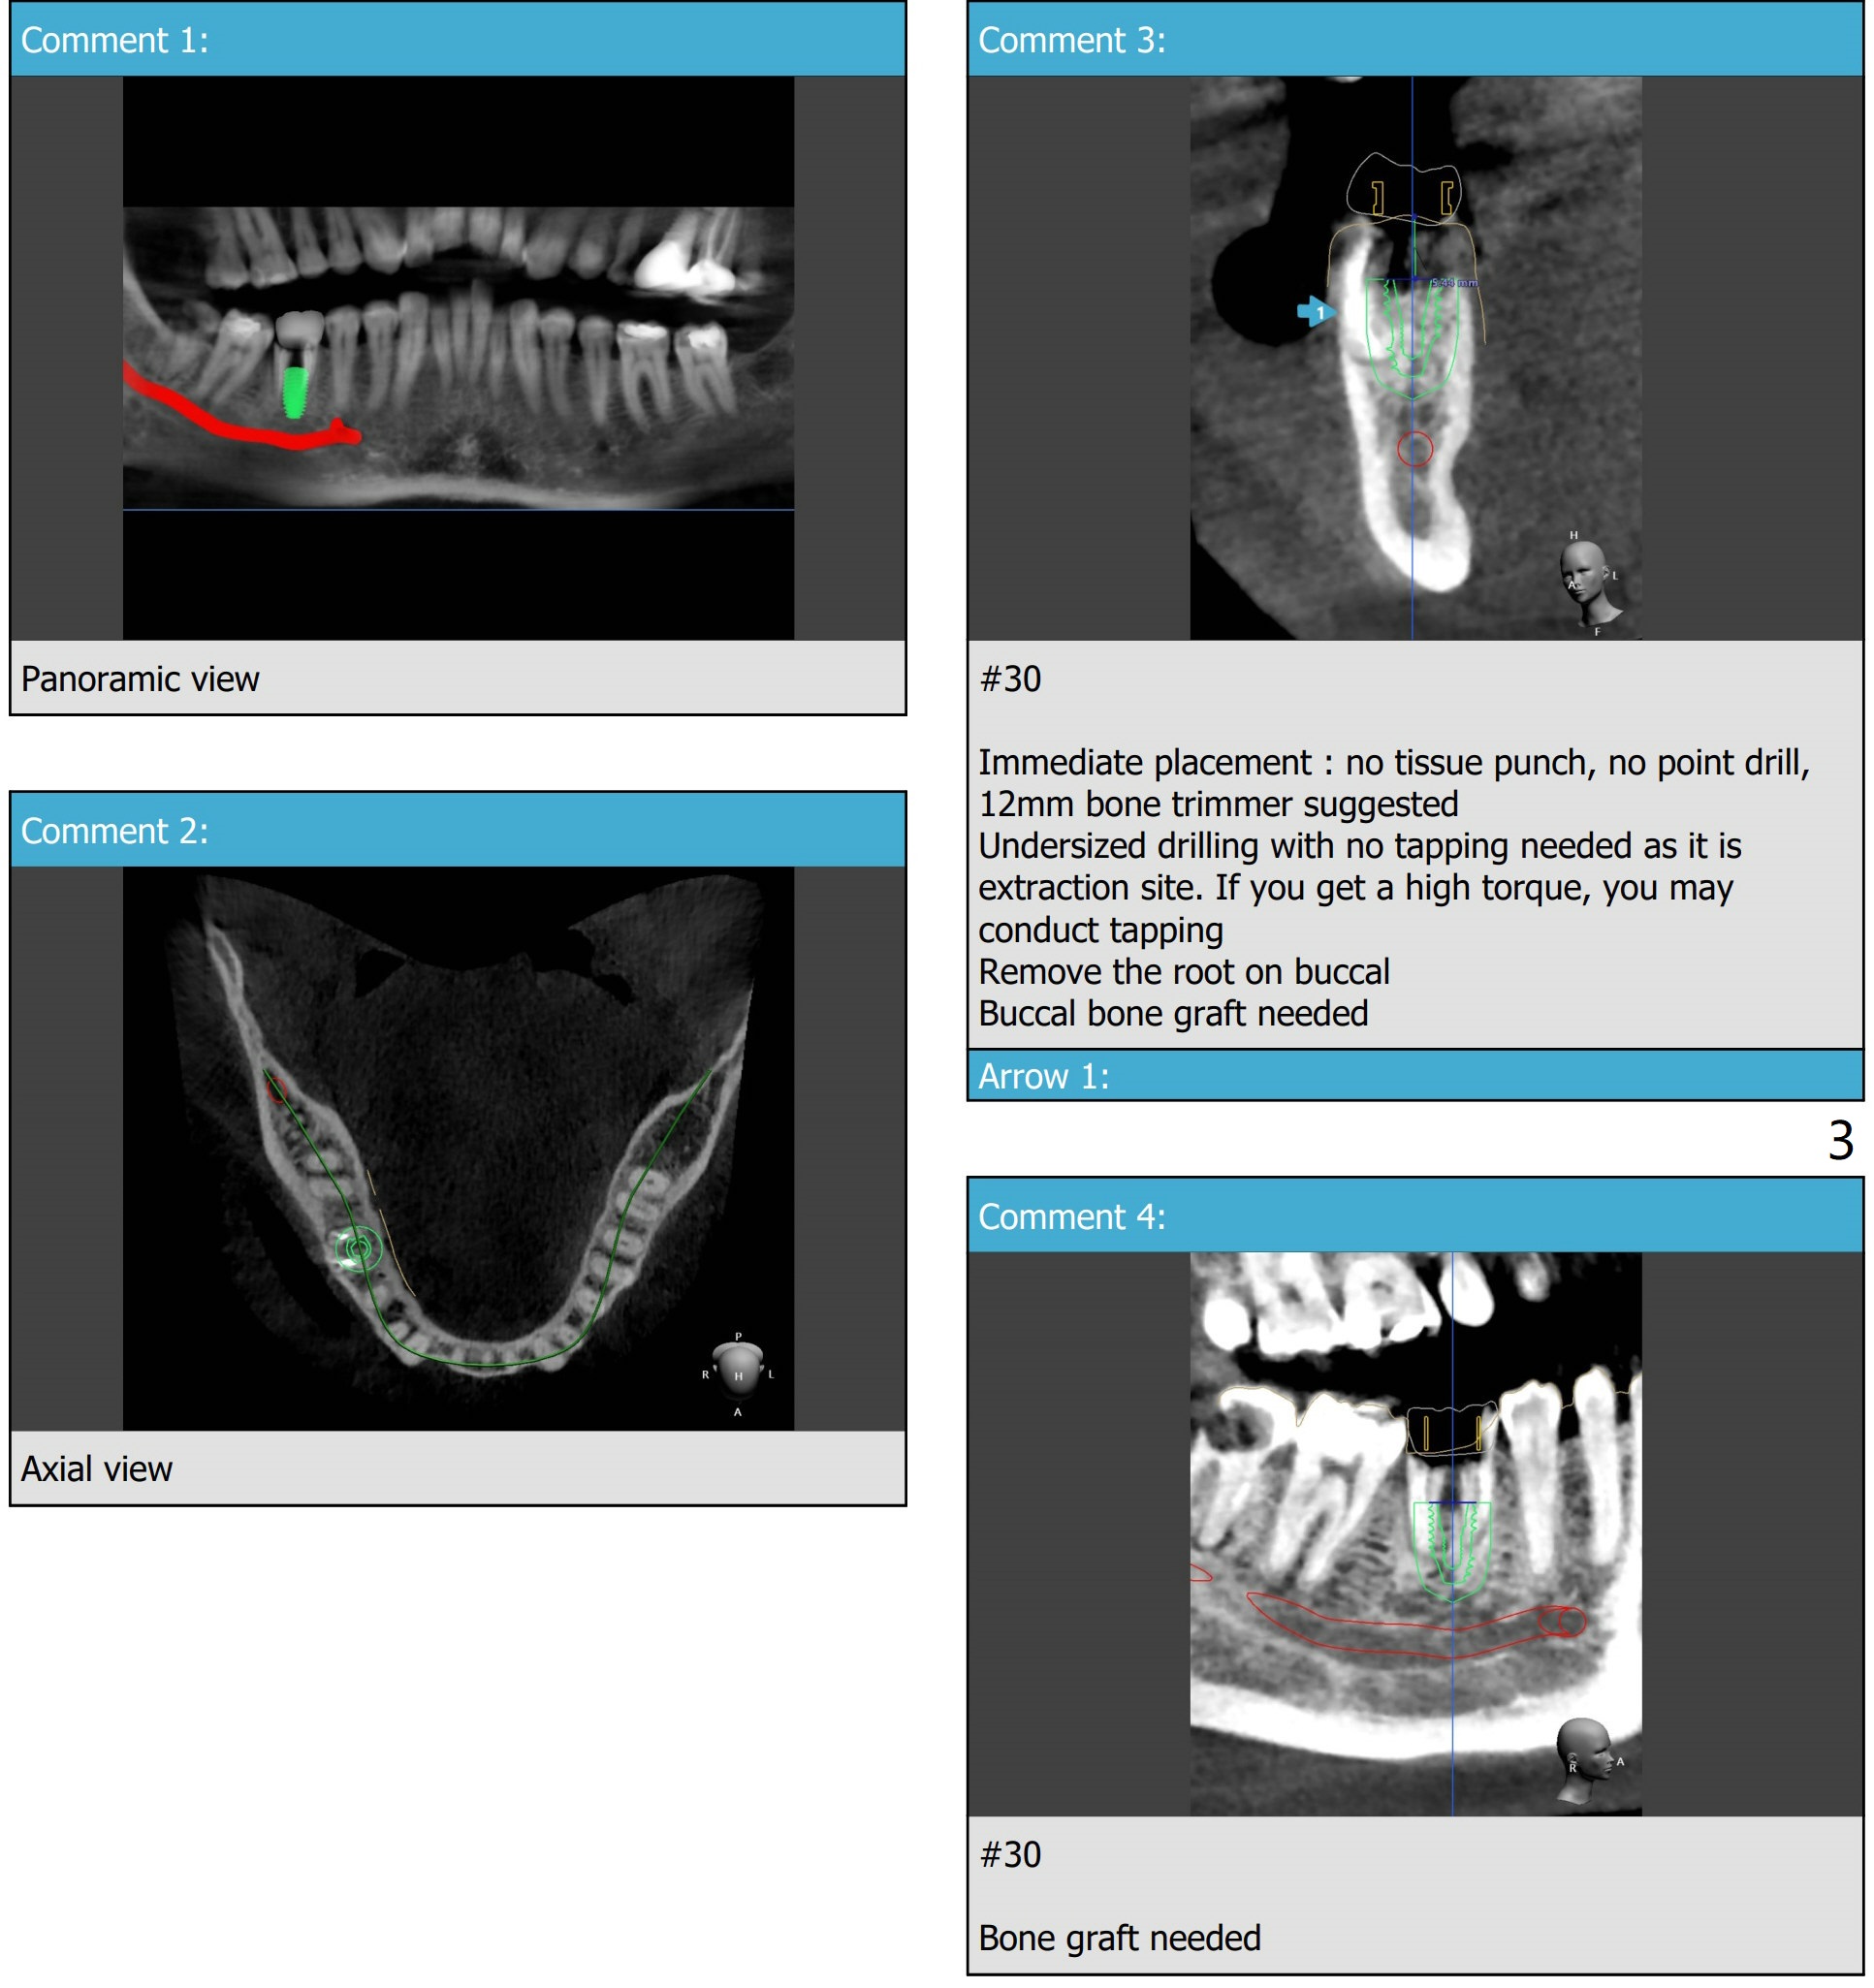

A 53-year-old man. PRFx1. Place 5x11 mm Tatum tapered implant (9 mm in bone).